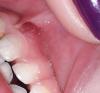

Здравствуйте девочки! Подскажите пожалуйста у дочи на верхней десне какая та шишка! Что это может быть может кто то сталкивался? Фото в комментариях

Не знаю как называется,но у меня раньше часто выходила такое, я сама с зубами его лопнула,потом прошло